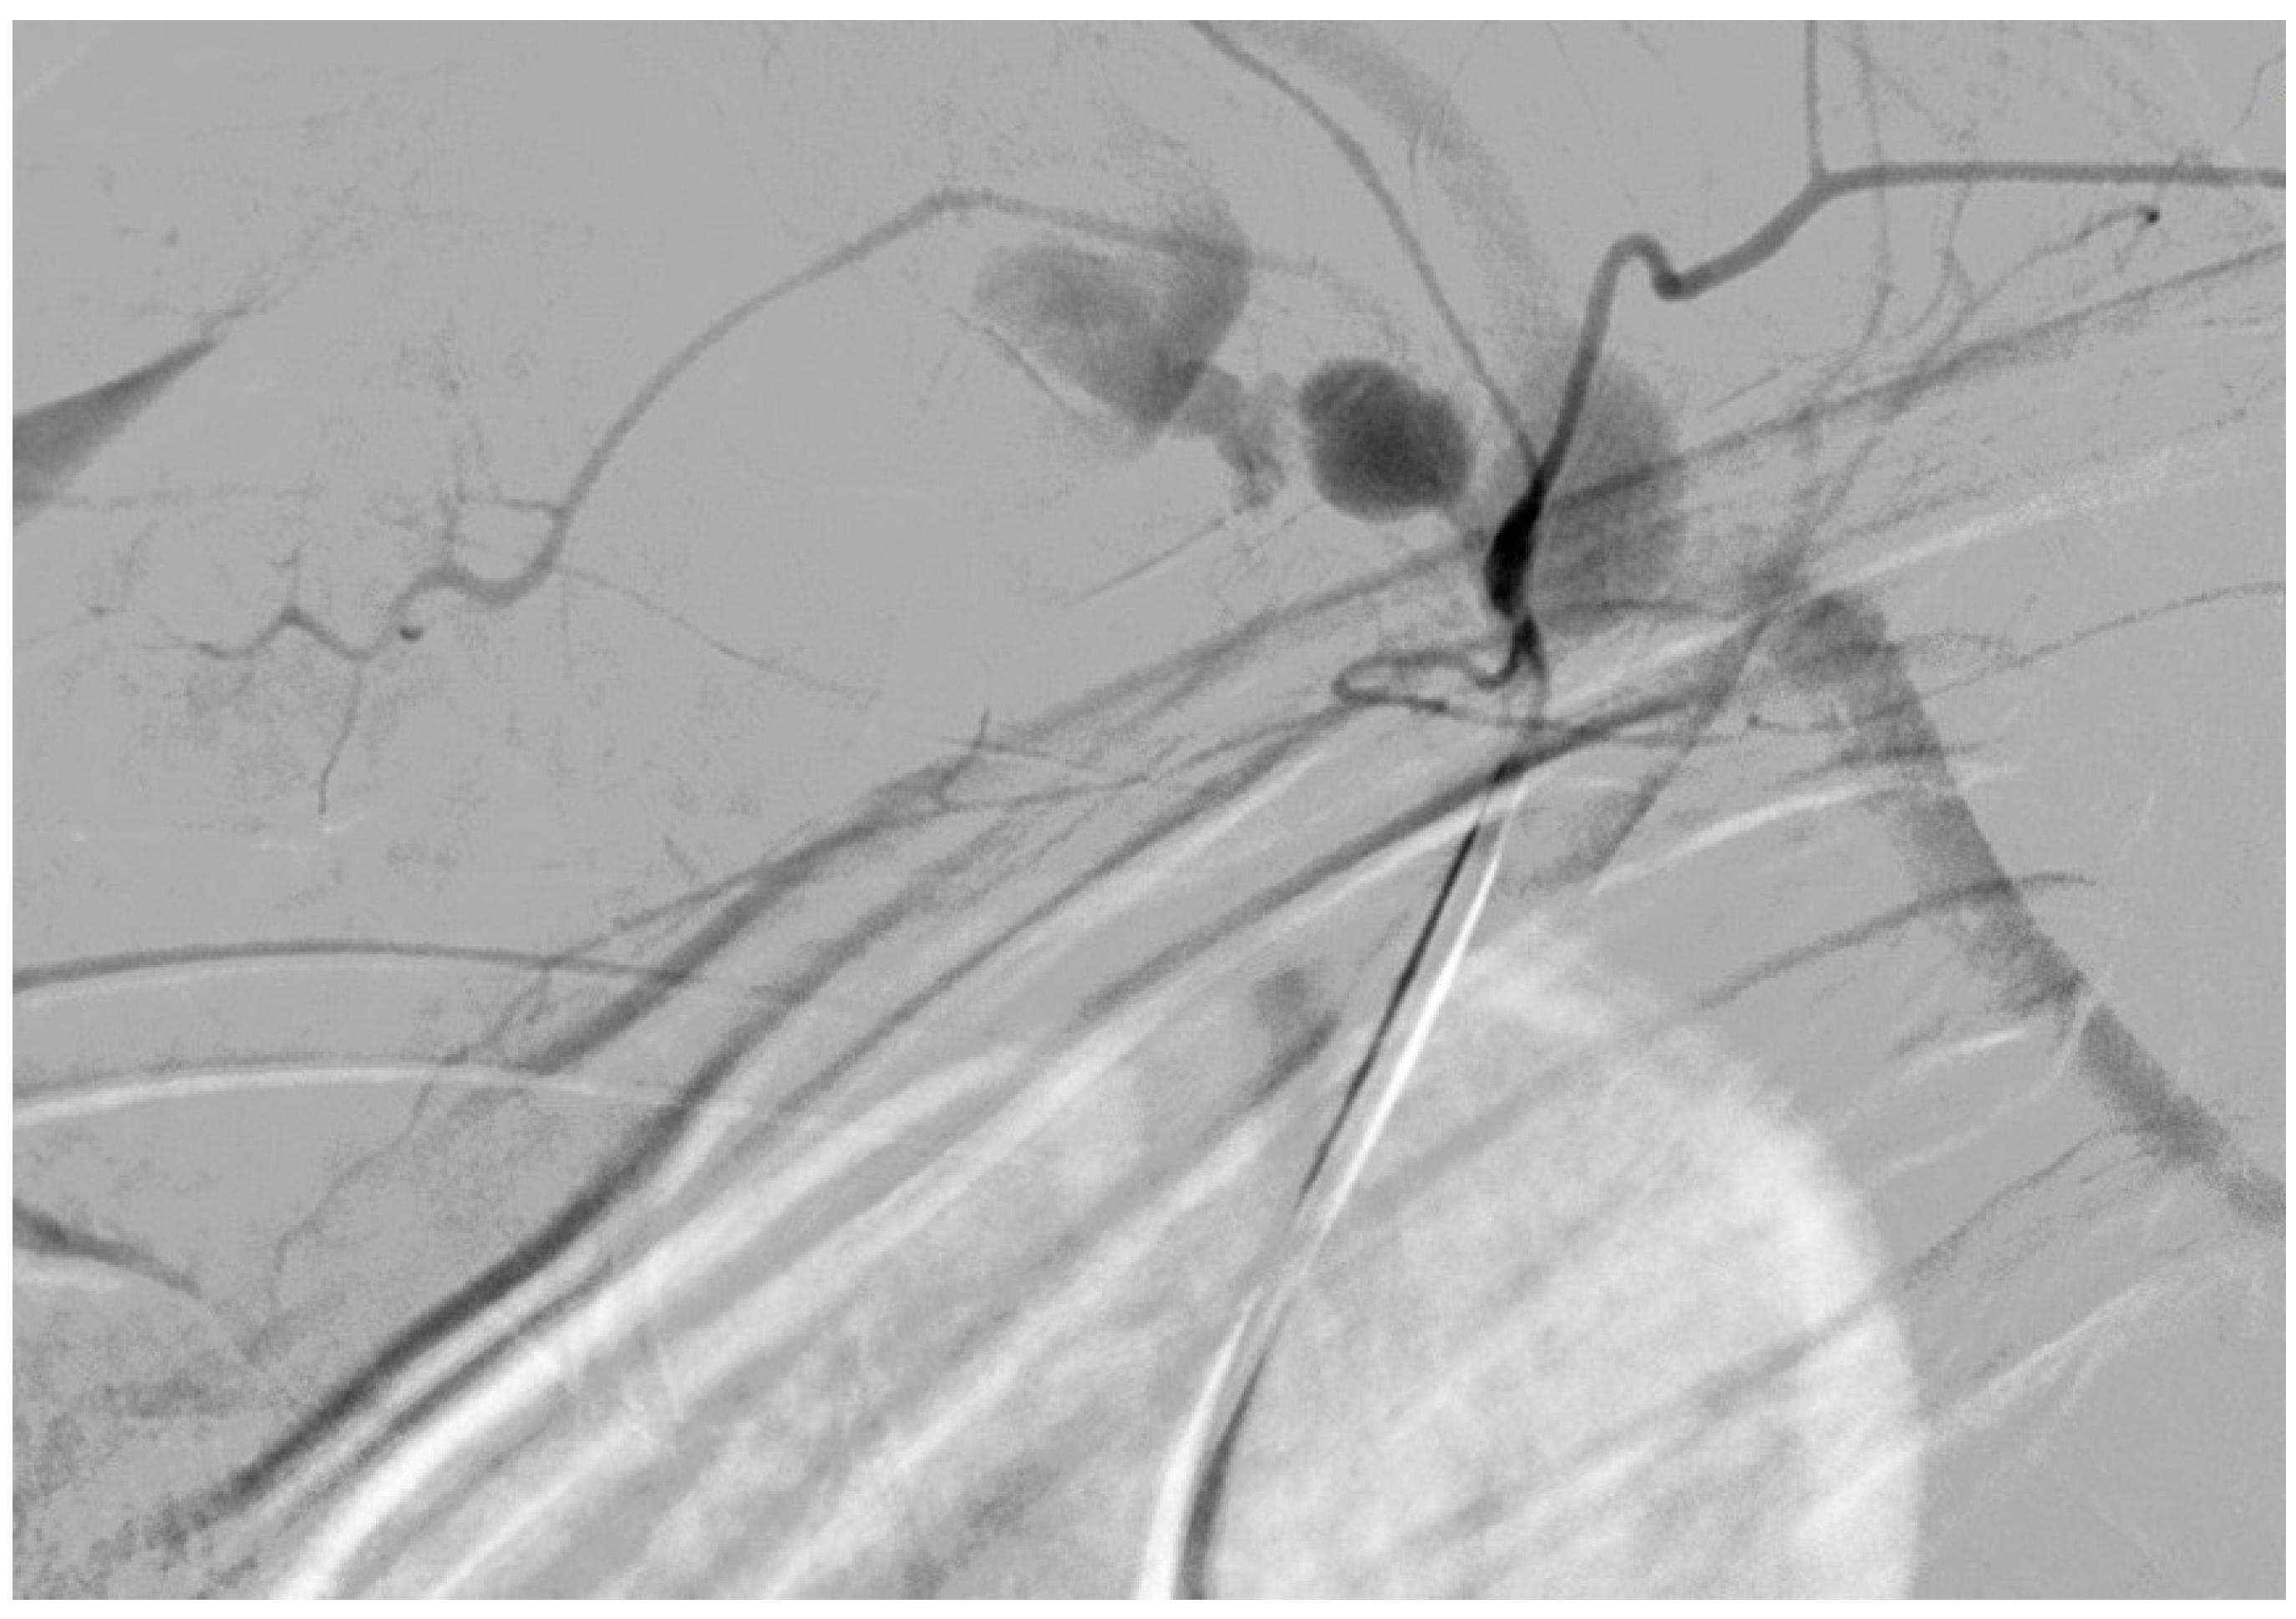

Successful Management of Thyrocervical Trunk Aneurysm Ruptured into the Thoracic Cavity After Cesarean Section in Nonstable Patient with Neurofibromatosis Type I

2. Case Description